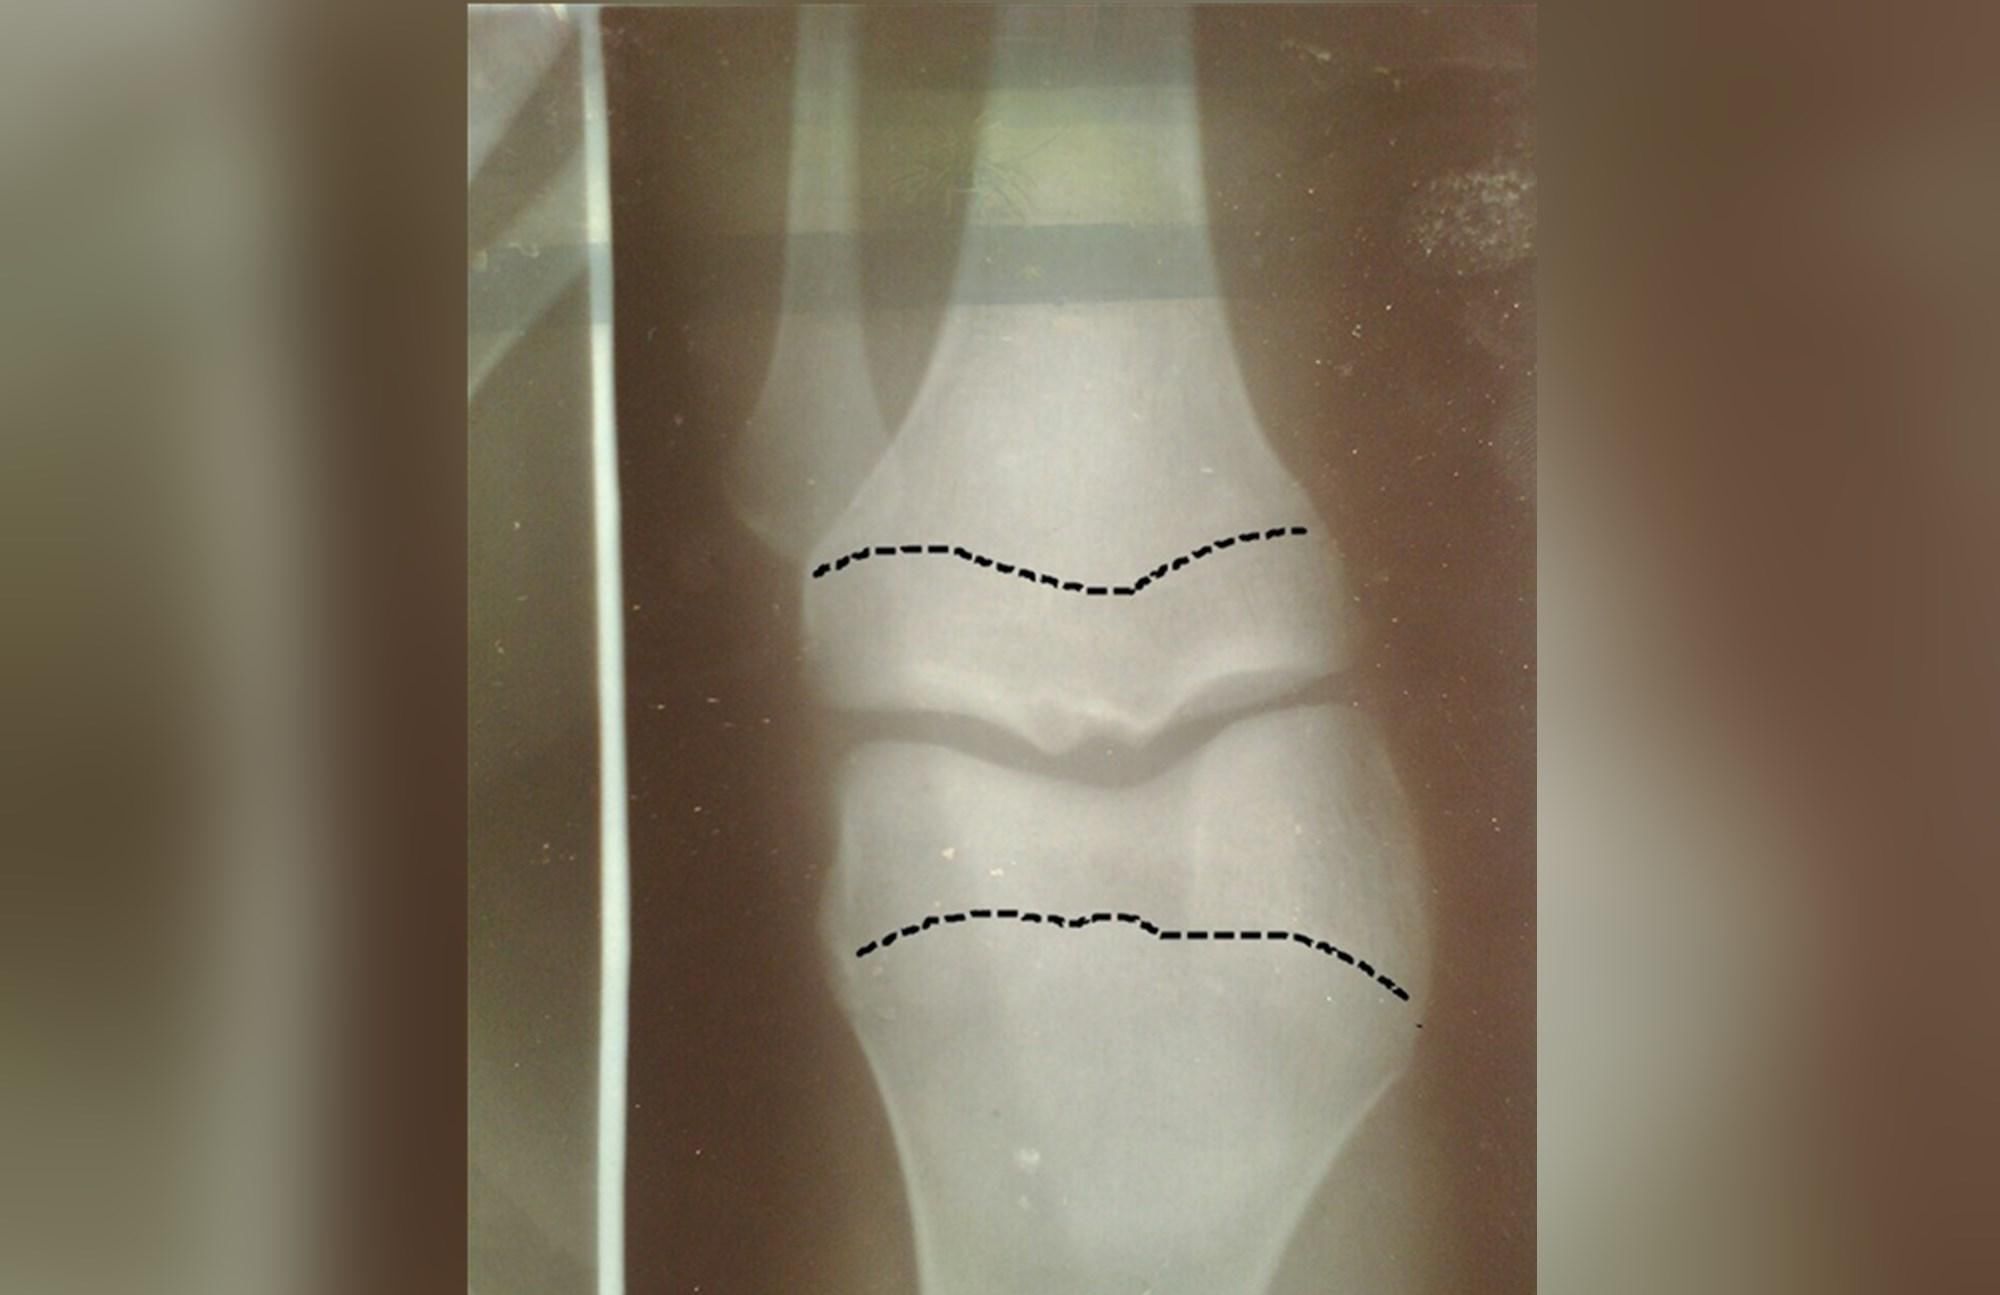

骨骼线其实是一种形象化的称呼,骨骼线其实是一种软骨,这种软骨的特殊性在于能够随着生长而发生骨化。而在骨骼这个软骨发生骨化后会形成一条缝,这说明骨骼线完全闭合,骨骼也会随之停止发育。